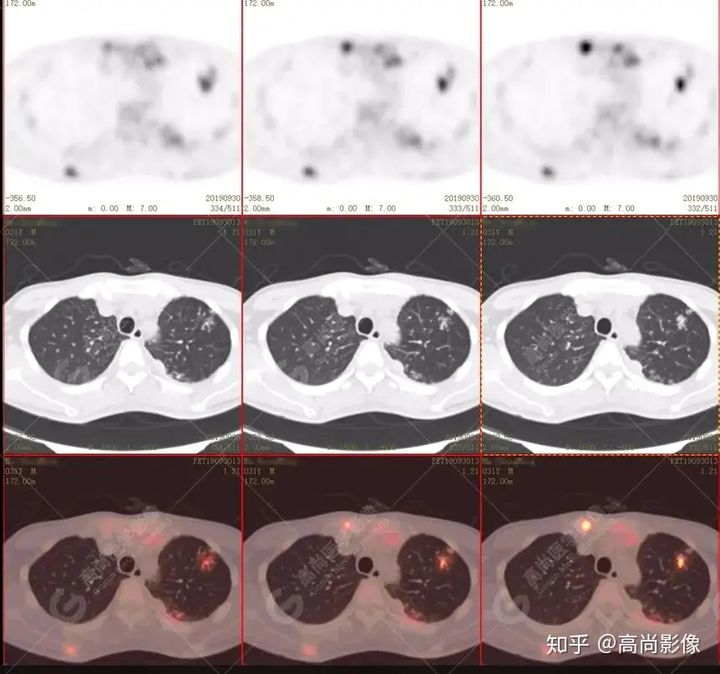

左肺上葉尖后段及下葉背段多發(fā)簇狀斑點(diǎn)狀高代謝灶

左側(cè)胸膜結(jié)節(jié)樣增厚,代謝不同程度增高

【PET/CT提示】雙肺、左側(cè)胸膜多發(fā)結(jié)節(jié)影,全身多處骨質(zhì)破壞,全身多發(fā)淋巴結(jié)腫大,代謝攝取不均勻性增高。

特征:肺部病灶簇狀分布,上葉尖段及下葉背段為著;腫大淋巴結(jié)分布不對(duì)稱,無(wú)融合、中央有壞死改變,與淋巴瘤、轉(zhuǎn)移瘤等有一定的鑒別診斷意義;

好發(fā)上葉尖后段及下葉背段(血氧飽和度豐富);